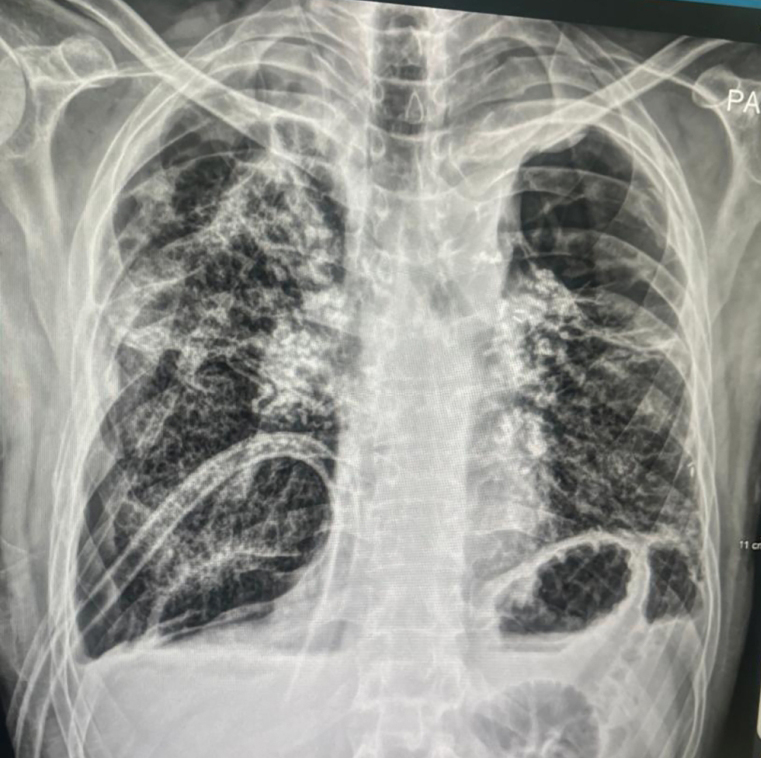

ويعاني (أبوياسين - مصري - 44 عاماً) فشلاً رئوياً حاداً، ويعيش على جهاز الأوكسجين، بانتظار أن يتمكن من إجراء عملية لزراعة رئة، ووفقاً لمستشفى كليفلاند أبوظبي، فإن المريض يحتاج إلى زراعة رئة في أسرع وقت ممكن، نظراً إلى سوء حالته الصحية.

وروى (أبوياسين) لـ«الإمارات اليوم»، أن معاناته مع المرض بدأت عام 2013، إذ عانى وجود تليف بسيط في الرئة، وكان علاجه قاصراً على تناول الأدوية، لكن حالته بدأت تزداد سوءاً يوماً بعد الآخر، فيما كان التليف يزداد ومساحته تتسع.

وقال إن الأدوية التي كان يتناولها تضمنت الكورتيزون، مضيفاً: «بعد فترة، توقف الجزء الأيسر من الرئة، وأصبحت أعيش على رئة واحدة، ودخلت إلى وحدة العناية المركزة في مدينة الشيخ خليفة بن زايد الطبية، حيث رقدت لفترة تحت الملاحظة الطبية».

وأضاف: «قبل نحو عام، تعرّضت لحادث مروري وتضررت الرئة اليمنى، وبدأت تضعف، إلى أن فقدت قدرتها على العمل، وحالياً أعيش على جهاز الأوكسجين على مدار اليوم، ولا أستطيع الاستغناء عنه».

وقال: «دخلت إلى مستشفى كليفلاند في أبوظبي، وبعد إجراء الفحوص والتحاليل والمعاينة الطبية لي، تبيّن أنني أحتاج إلى زراعة رئة، باعتباري وصلت إلى مرحلة الفشل الرئوي».